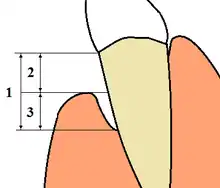

Severity

The "severity" of disease refers to the amount of periodontal ligament fibers that have been lost, termed "clinical attachment loss". According to the 1999 classification, the severity of chronic periodontitis is graded as follows:[66]

- Slight: 1–2 mm (0.039–0.079 in) of attachment loss

- Moderate: 3–4 mm (0.12–0.16 in) of attachment loss

- Severe: ≥ 5 mm (0.20 in) of attachment loss

Extent

The "extent" of disease refers to the proportion of the dentition affected by the disease in terms of percentage of sites. Sites are defined as the positions at which probing measurements are taken around each tooth and, generally, six probing sites around each tooth are recorded, as follows:

Dentists and dental hygienists measure periodontal disease using a device called a periodontal probe. This thin "measuring stick" is gently placed into the space between the gums and the teeth, and slipped below the gumline. If the probe can slip more than 3 mm (0.12 in) below the gumline, the person is said to have a gingival pocket if no migration of the epithelial attachment has occurred or a periodontal pocket if apical migration has occurred. This is somewhat of a misnomer, as any depth is, in essence, a pocket, which in turn is defined by its depth, i.e., a 2-mm pocket or a 6-mm pocket. However, pockets are generally accepted as self-cleansable (at home, by the person, with a toothbrush) if they are 3 mm or less in depth. This is important because if a pocket is deeper than 3 mm around the tooth, at-home care will not be sufficient to cleanse the pocket, and professional care should be sought. When the pocket depths reach 6 to 7 mm (0.24 to 0.28 in) in depth, the hand instruments and ultrasonic scalers used by the dental professionals may not reach deeply enough into the pocket to clean out the microbial plaque that causes gingival inflammation. In such a situation, the bone or the gums around that tooth should be surgically altered or it will always have inflammation which will likely result in more bone loss around that tooth. An additional way to stop the inflammation would be for the person to receive subgingival antibiotics (such as minocycline) or undergo some form of gingival surgery to access the depths of the pockets and perhaps even change the pocket depths so they become 3 mm or less in depth and can once again be properly cleaned by the person at home with his or her toothbrush.